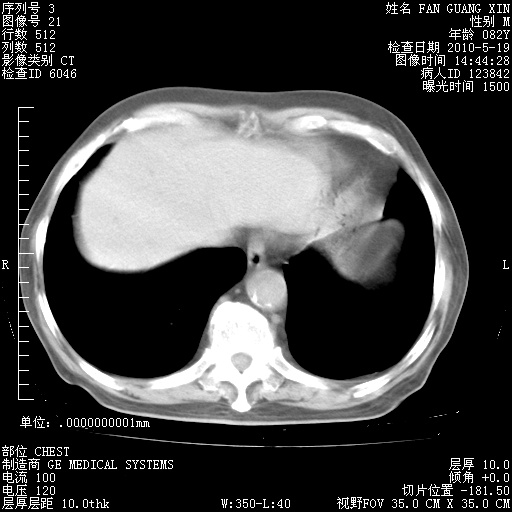

治疗3周后的肺部CT纵隔窗

阅读此次胸部CT,肺间质渗出性改变较入院时有吸收。目前从体温、白细胞、中性分叶明显增高,肯定存在细菌感染(发生医院感染哦,若无消化道及泌尿系统等感染的依据,肺部感染可能大)。若你院头孢哌酮舒巴坦钠耐药率较高,同意你的方案,若48小时体温仍高,可考虑使用碳青霉稀类抗菌药物,同时可予超声雾化、注意滴数时加大液体量。白蛋白33.30g/L较低哦,需加强营养等支持治疗。